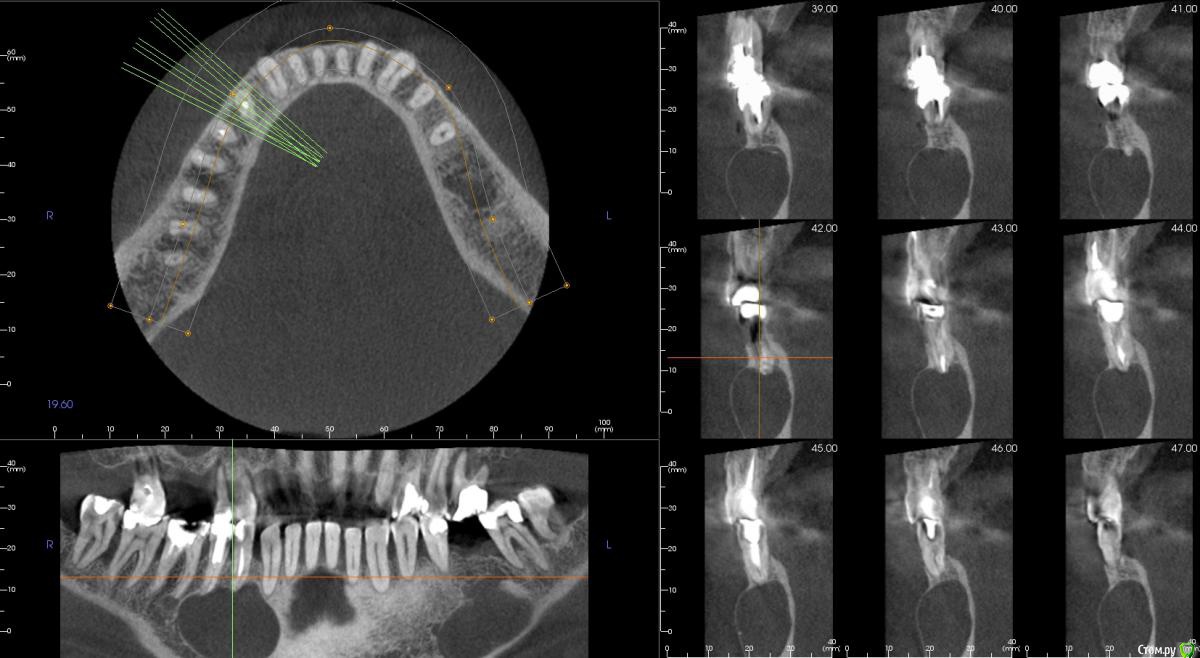

kamranchick Опубликовано 1 сентября, 2015 Поделиться Опубликовано 1 сентября, 2015 Не подскажите что с пациентом? пришел ставить мосты снизу и сверху, отправили на ОРТО, а тут такое... Ссылка на комментарий

kamranchick Опубликовано 2 сентября, 2015 Автор Поделиться Опубликовано 2 сентября, 2015 Артефакт наверное)сначала прицельный сделали, потом панорамный, потом на кт, везде одна и та же картина была Ссылка на комментарий

JDS Опубликовано 2 сентября, 2015 Поделиться Опубликовано 2 сентября, 2015 А может обширная генерализованная радикулярная киста?? Слева будто резидуальная. Не буду тыкать в небо, дождемся ответа опытных))) Ссылка на комментарий

kamranchick Опубликовано 2 сентября, 2015 Автор Поделиться Опубликовано 2 сентября, 2015 В онко понятно, а предварительный хоть какой диагноз поставите?? Жалобы пациент предъявляет??Жалоб никаких абсолютно нет, во рту ничего не пальпируется, слизистая в норме, зубы также Ссылка на комментарий

pigmaleon Опубликовано 2 сентября, 2015 Поделиться Опубликовано 2 сентября, 2015 Радикулярная и резидуальная кисты. 1 Ссылка на комментарий